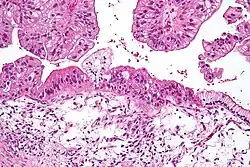

| Intermediate magnification micrograph of a low malignant potential (LMP) mucinous ovarian tumour. H&E stain.

The micrograph shows: Simple mucinous epithelium (right) and mucinous epithelium that pseudo-stratifies (left - diagnostic of a LMP tumour). Epithelium in a frond-like architecture is seen at the top of image. | |